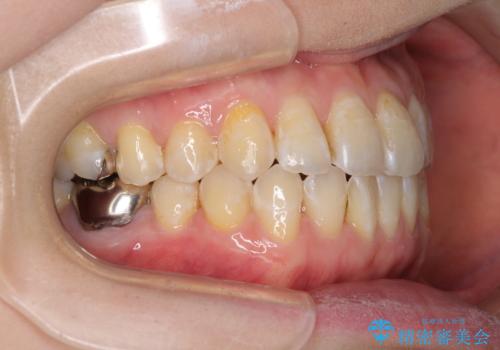

前歯のデコボコを治したい インビザラインによる矯正治療

- 前歯のデコボコを治したいとのことで来院された患者様です。

上下顎ともに歯列全体の後方移動とIPR(歯と歯の間を削る)によってデコボコが解消するように設計し、インビザラインにより治療を行うこととしました。

1日22時間の装着時間をほとんど達成することができず、治療には当初予定の2倍以上の期間を要することとなりました。